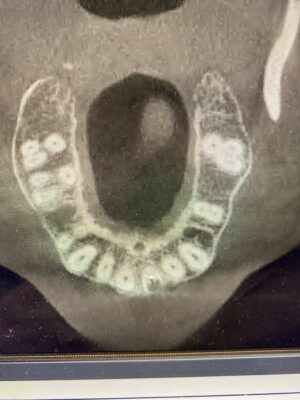

If you have time for another – how would you manage this case? 33yr old male with a chronic abscess and draining sinus tract from tooth 21 (or 9). External resorption on the middle to apical parts of the root were confirmed in CBCT. What type of bone grafting would need to be done / ie how do you repair the buccal plate? how long do you wait to graft after the initial extraction is done? Do you provide an essix as a temporary?

Here are his scans. Not sure if this bite is entirely accurate but there is no contact on the two centrals.